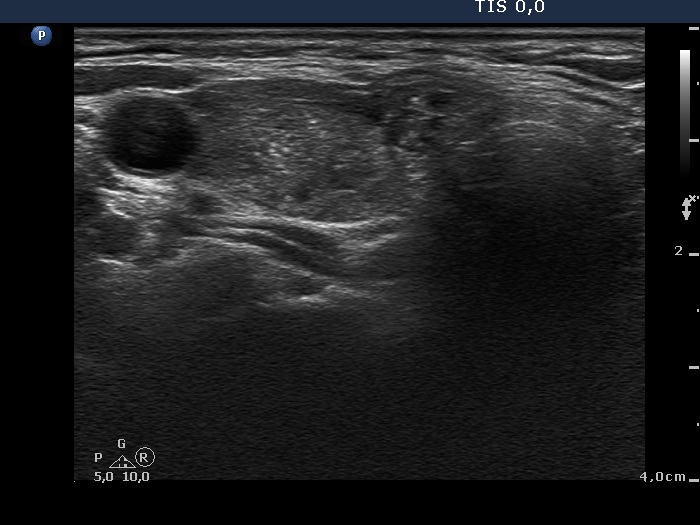

Benign hyperplastic nodule (histological diagnosis) - case 837 |

Papillary carcinoma in Hashimoto's thyroiditis (histological diagnosis) - case 455 |

The bright granules partly have dorsal tail, these are therefore comet-tail artifacts. Moreover, this is a small cyst; therefore the granules within the fluid cannot be anything other than colloid crystals.

There are large bright granules in the lower, longitudinal image. With this older equipment these figures might be punctate echogenic foci.